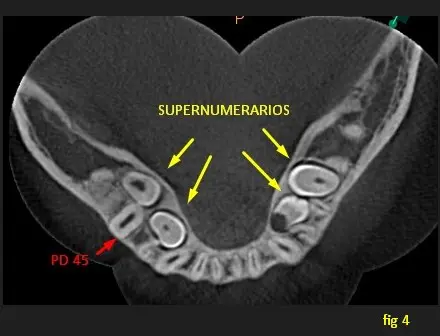

En la vista axial (imágen 4) y en los cortes transaxiales (imágenes 5 y 6) se observa a todos los supernumerarios ubicados dentro de ambas tablas corticales y con una ubicación lingual respecto a las pd normales, además se observa la ubicación exacta de la pieza dentaria 45 retenido y su relación con el supernumerario (impactación).